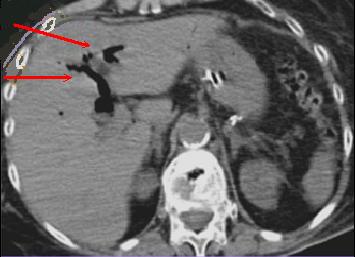

Boudin invagination

ileo-coecale du tumeur villeuse ( fleche rouge

) resoponsable une occlusion . Image TDM en coupe

axiale . |

| Image TDM en coupe axiale : Invagination

ileo- colique |